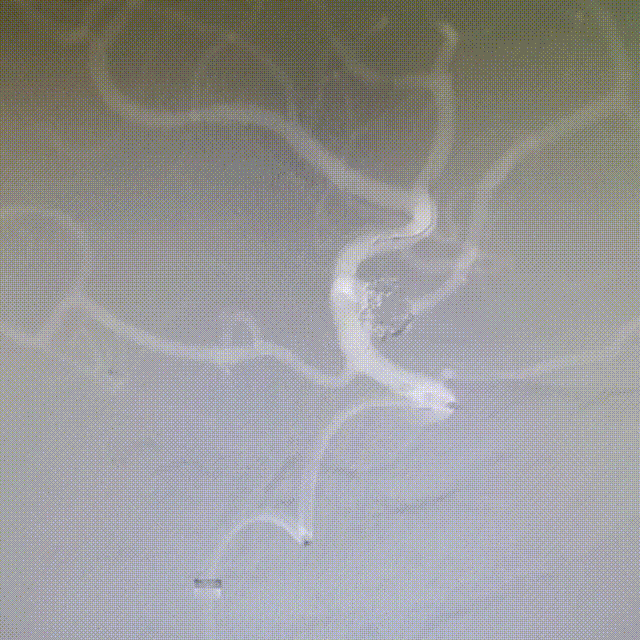

术后即刻工作位造影显示,支架全程打开形态良好,充分贴壁。

术后即刻正/侧位造影显示:各分支血管血流通畅,无出血情况,瘤体内无造影剂充盈。

术后3D造影:支架打开充分,全程贴壁,各分支血管血流通畅,可看到内翻的Mark点也被Evolve贴到了血管壁上,充分体现了Evolve足够强的径向力,预示着Evolve对动脉瘤合并狭窄应用或许是一个不错的选择。